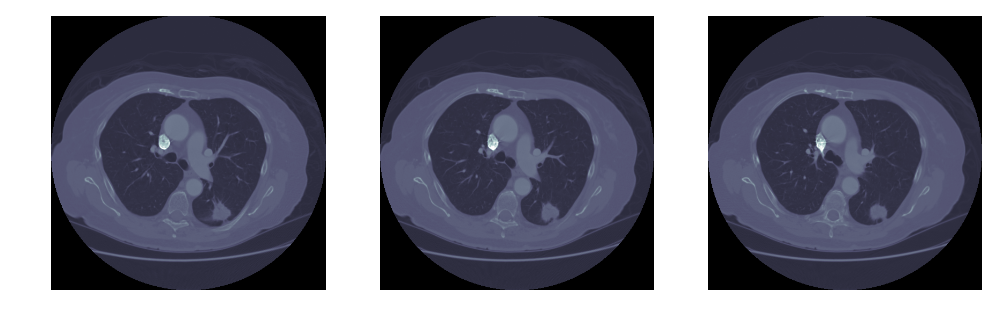

然后,我们看一下读取的结果。可见输入文件中标注的结节就在右下方。

可见图中,除了中间亮度较低的肺部,还有亮度较高的脊柱、肋骨,以及肌肉、脂肪等组织。我们的一个思路,就是 留下暗的区域,去掉亮的区域。当然这里,亮度多高才算亮?这个我们可以对一张图中所有像素点的亮度做概率密度分布,然后用 Kmeans 算法,找出这个明暗分解的阈值(下文图中左上角):